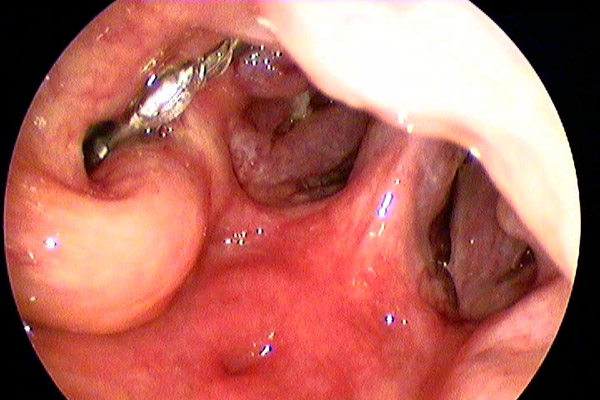

Tubenkatheter nach Platzierung in der Öffnung der Eustachischen Röhre im Nasenrachen.

Beim Zurückziehen des Ballons aus der Tube entleert sich häufig Schleim aus der Eustachischen Röhre.